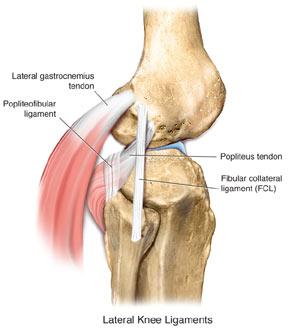

외측인대는 앞측 비골 근위부와 원위 대퇴골(lateral epicondyle) 사이에 붙어있습니다.

따라서 이러한 인대의 위치가 늘어나거나 다쳤다는 생각을 하면서 치료를 해야합니다.